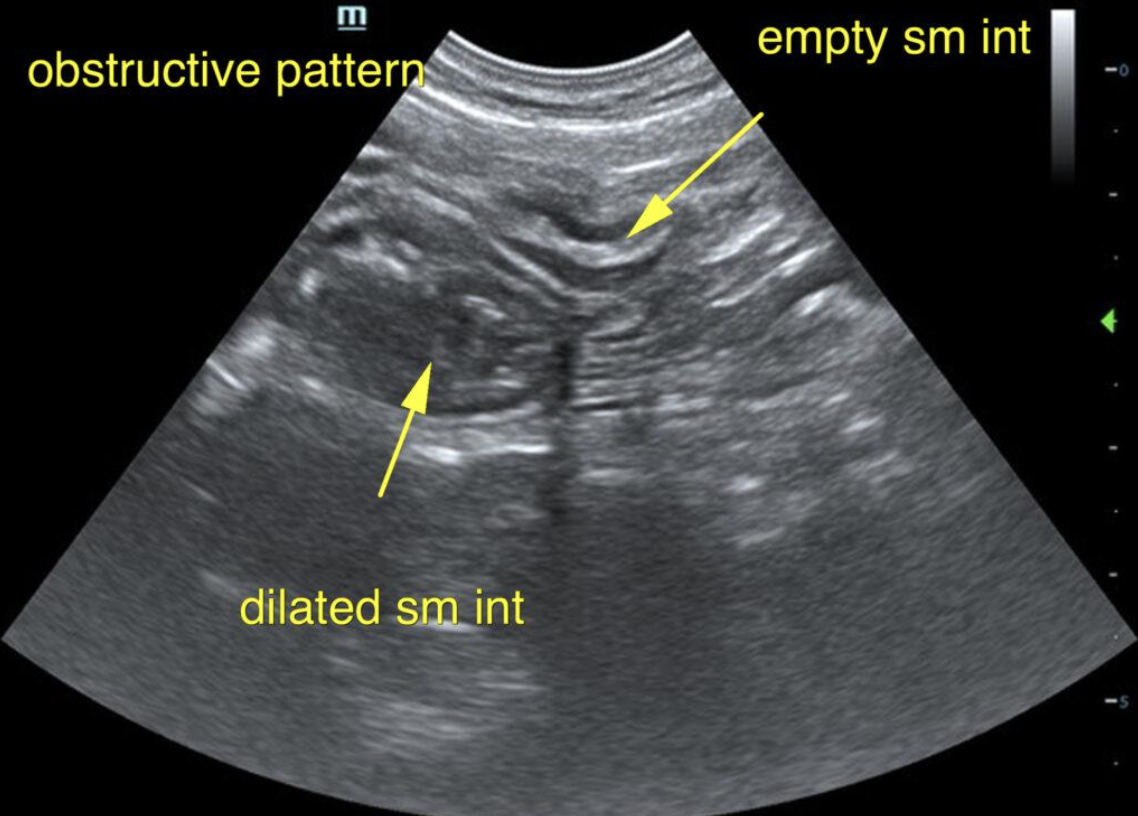

Our experienced SDEP® certified technicians, Kelly Reschny, RVT & Crystal Hill, RVT will come to your clinic and perform a diagnostic ultrasound on your patient. The images will then be submitted to a SonoPath specialist who will provide a comprehensive report. The report will include sonographic findings, internal medicine diagnostics and treatment recommendations with annotated images identifying any pathology or areas of concern. If needed, our technicians can perform ultrasound-guided fine needle aspirates, abdominocentesis or pericardiocentesis.

The Focal Zone fueled by Sonopath, a mobile veterinary ultrasound service, gives you a sneak peek on its monthly Star Cases.

VSD, CHF, and Thoracic Mass In A 4-Year-Old Intact Male Sphynx Cat: Our 2023 Star…

Retrobulbar Mass – Right Eye In A 4-Year-Old, MN, English Setter: Our 2023 Star Cases